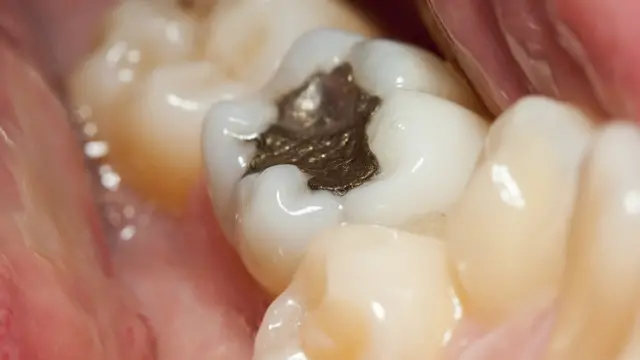

До пришествия в стоматологию ртутной амальгамы в 1830-х годах, для пломбирования зубов использовалось множество различных металлов, включая свинец, олово, серебро и различные сплавы.

Андреа Селла, профессор неорганической химии в Университетском колледже Лондона, указывает на то, что если для пломбирования использовались два различных металла, то это могло привести к образованию электрохимической ячейки.

Фактически рот пациента превращался в низковольтную батарею.

"В результате соседства во рту различных металлов там мог внезапно начаться процесс электролиза. Я отдаю предпочтение объяснению, согласно которому в случае некачественного пломбирования часть полости дупла остается не заделанной, что может привести к скоплению водорода внутри зуба".